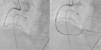

She was scheduled for primary angioplasty, which could not be performed by a radial approach due to the tortuosity of the subclavian artery (Figure 1A) and femoral access was hampered by absence of a pulse, and so a contrast-guided puncture was performed (Figure 1B and C). The external iliac artery was found to be occluded, but was passed using a hydrophilic guidewire. The mid segment of the right coronary artery was occluded by a thrombus (Figure 2A), which was removed by thrombectomy (Figure 2B).

Left heart catheterization: (A) radial access made impossible due to the tortuosity of the subclavian artery, which prevented passage of the guidewire; (B) contrast-guided puncture of the left femoral artery; (C) catheterization by femoral access revealing a mobile thread-like structure (arrow), consistent with a thrombus.